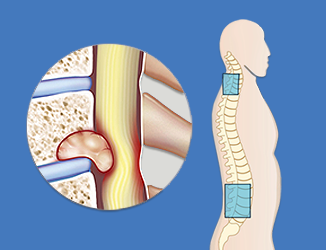

Value added benefits of the Vertebral Angioplasty:

Ø Doctor consultation charges

Ø Lab tests and diagnostic charges

Ø Room charges inside hospital during the procedure

Ø Surgeon Fee

Ø Nursing charges

Ø Hospital surgery suite charges

Ø Anesthesia charges

Ø Routine medicines and routine consumables (bandages, dressings etc.)

Ø Food and Beverages inside hospital stay for patient and one attendant.